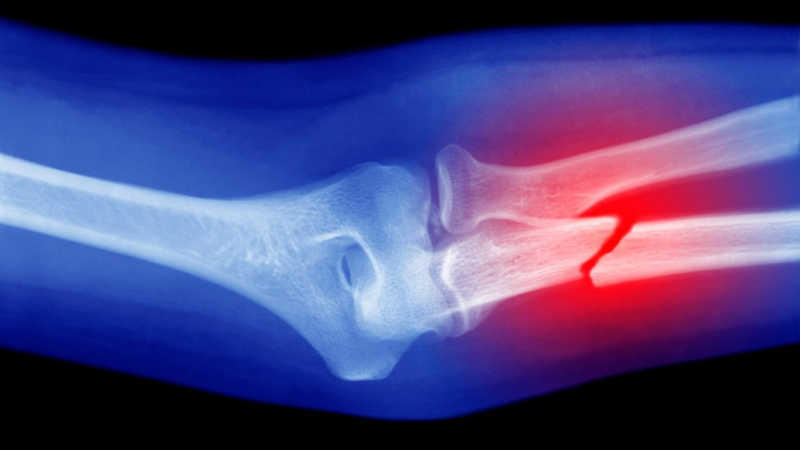

Исследователи продемонстрировали технологию, модифицировав пистолет для горячего клея для 3Д-печати материала непосредственно на переломах костей у кроликов. Вместо использования обычного клеевого стержня они использовали специально изготовленную “биоинку”, сообщает команда 5 сентября в журнале Device.

Ли и его коллеги протестировали клеевой пистолет и биоинк на переломах бедренной кости у кроликов. Сравнивая результаты у кроликов, получавших терапию, с контрольной группой, получавшей обычный костный цемент, команда обнаружила, что у первой группы было лучшее заживление и регенерация костной ткани. У животных также не было никаких признаков инфекции в течение 12 недель после операции.